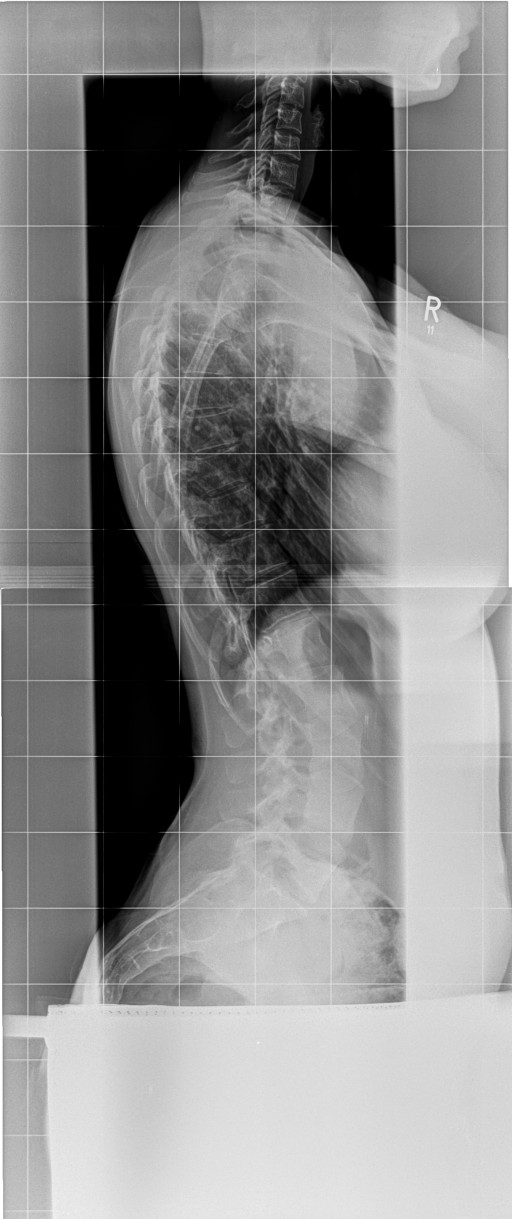

Diagnose: Skoliose LWS 41 Grad ( idiopathisch ) Kyphose 40 Grad

Bei mir steht der Brustknochen, bzw das Sternum total hervor ( siehe Bild , Datei ) In der Werner Wicker Klinik, sowie in Neustadt sagte man mir der vorstehende Brustknochen bzw das Sternum hätte nichts mit der Skoliose zu tun ?!? Aber die Wirbelsäule ist doch in sich verdreht, also hat es eigentlich doch etwas damit zu tun oder ? Vor 10 Jahren hatte ich diesen extremen Knochen nämlich noch nicht. Weis darüber jemand etwas ?

6.jpg

Aufnahme Herbst 2017

Sternum das immer weiter raus ragt